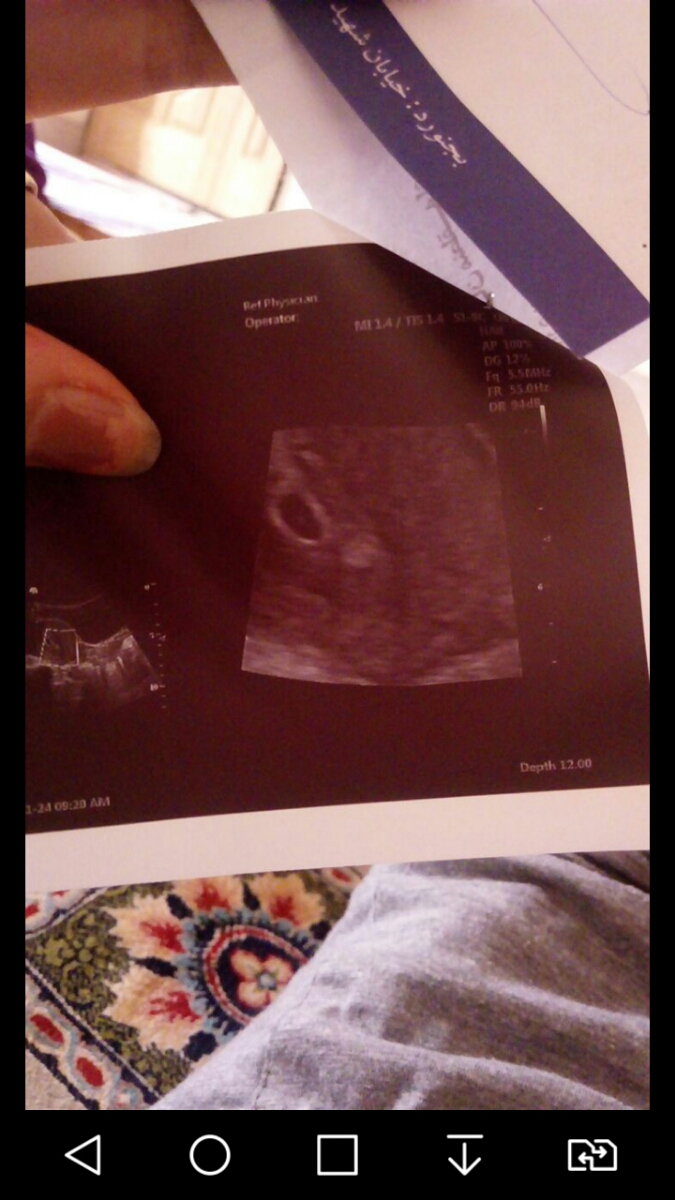

من 2روز پریودم عقب افتاده متوجه شدم باردارم الان رفتم سونو ساک حاملگی تشکیل شده اما جنین دید نشده نوشته yolk sax خطر ناکه؟؟؟ دارم از استرس میمیرم زمان تقریبی هم زده 5هفته 5روز

عکسی سونو داده رو بفرست

برا منم دقیقا متن سونوی شما بود

بخون خودشم نوشته هنوزززز دیده نمیشه

ینی زوده

داده سونو تو کیف مامانمه انقد اعصابم داغون بود یه لحطه رفته بیرون اومد عکسشو میفرستم

اینم سونومه

نگران نباش منم سونو شکمی رفتم دقیقا 5هفته و5روز رفتم فقط ساک وکیسه زرده دیده شد و فاقد جنین بود

تقریبا8هفتم تمام شد رفتم برا قلبش

سلام در این سن بارداری تنها توقع رویت ساک است که گزارش شده برای قلب جنین اگر لکه بینی و خونریزی نداشتی هفته هشتم بارداری بروید